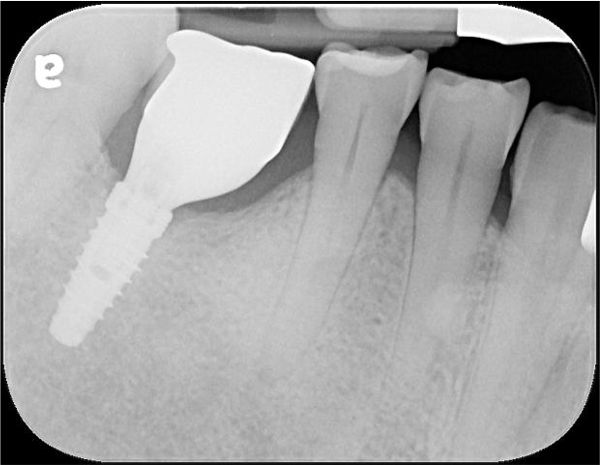

顯微根管治療

製作玻璃纖維釘柱